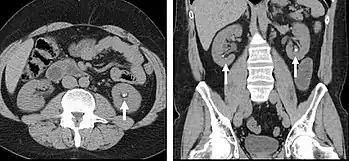

Non-contrast CT scans Figure 1a (left) and 1b (right) are of limited use for the differentiation of soft tissue structures. However, materials like blood, calcium (renal stones, vascular atherosclerosis), bone, and pulmonary parenchyma are highly visible and can usually be adequately assessed with non-contrast CT. For example, in the abdomen and pelvis, there are several indications for non-contrast imaging. These include: evaluation of renal calculi; assessment for gross intra-abdominal hemorrhage; and post-endostent volume measurements. In addition, non-contrast images are often obtained in conjunction with contrast enhanced images in evaluating potential renal transplant donors and in the evaluation of the pancreas (in combination with contrast phases). Of note, dual-energy CT and the development of virtual “non-contrast” images may ultimately obviate the combination scans. Additionally, CT angiography examinations performed for pathologies like aneurysms and dissection are frequently performed in conjunction with non-contrast imaging. The non-contrast images facilitate the differentiation of active extravasation or acute bleeding from vascular calcifications.